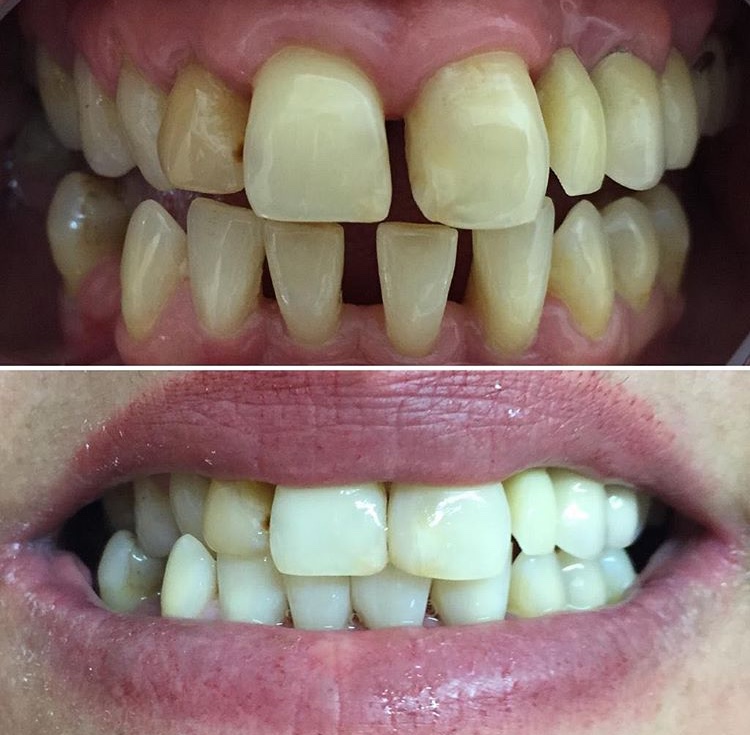

Cierre de diastema (espacio) dental con carillas (fundas)

El cierre de diastema es un tratamiento estético que corrige los espacios entre los dientes...